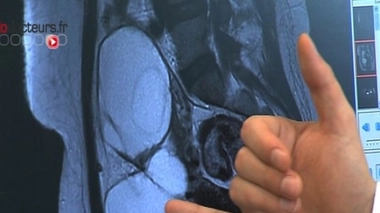

La structure d'un cervelet en formation retrouvée dans un ovaire

La structure d'un cervelet en formation retrouvée dans un ovaire - Image d'illustration (kyste ovarien)